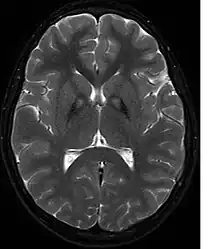

A neurological examination would show evidence of muscle rigidity; weakness; and abnormal postures, movements, and tremors. If other family members are also affected, this may help determine the diagnosis. Genetic tests can confirm an abnormal gene causing the disease. However, this test is not yet widely available. Other movement disorders and diseases must be ruled out. Individuals exhibiting any of the above listed symptoms are often tested using MRI (Magnetic Resonance Imaging) for a number of neuro-related disorders. An MRI usually shows iron deposits in the basal ganglia. Development of diagnostic criteria continues in the hope of further separating PKAN from other forms of neurodegenerative diseases featuring NBIA.

Microscopic features of PKAN include high levels of iron in the globus pallidus and the pars reticulata of substantia nigra, evident as a characteristic rust-brown discoloration[9] in a pattern called the eye-of-the-tiger sign;[10] lipofuscin and neuromelanin concentrated in the iron-accumulating areas; oval, nonnucleated structures representing swollen axons whose cytoplasm swells with vacuoles, referred to as spheroids, axon schollen, or neuroaxonal dystrophy; and Lewy bodies.[9]